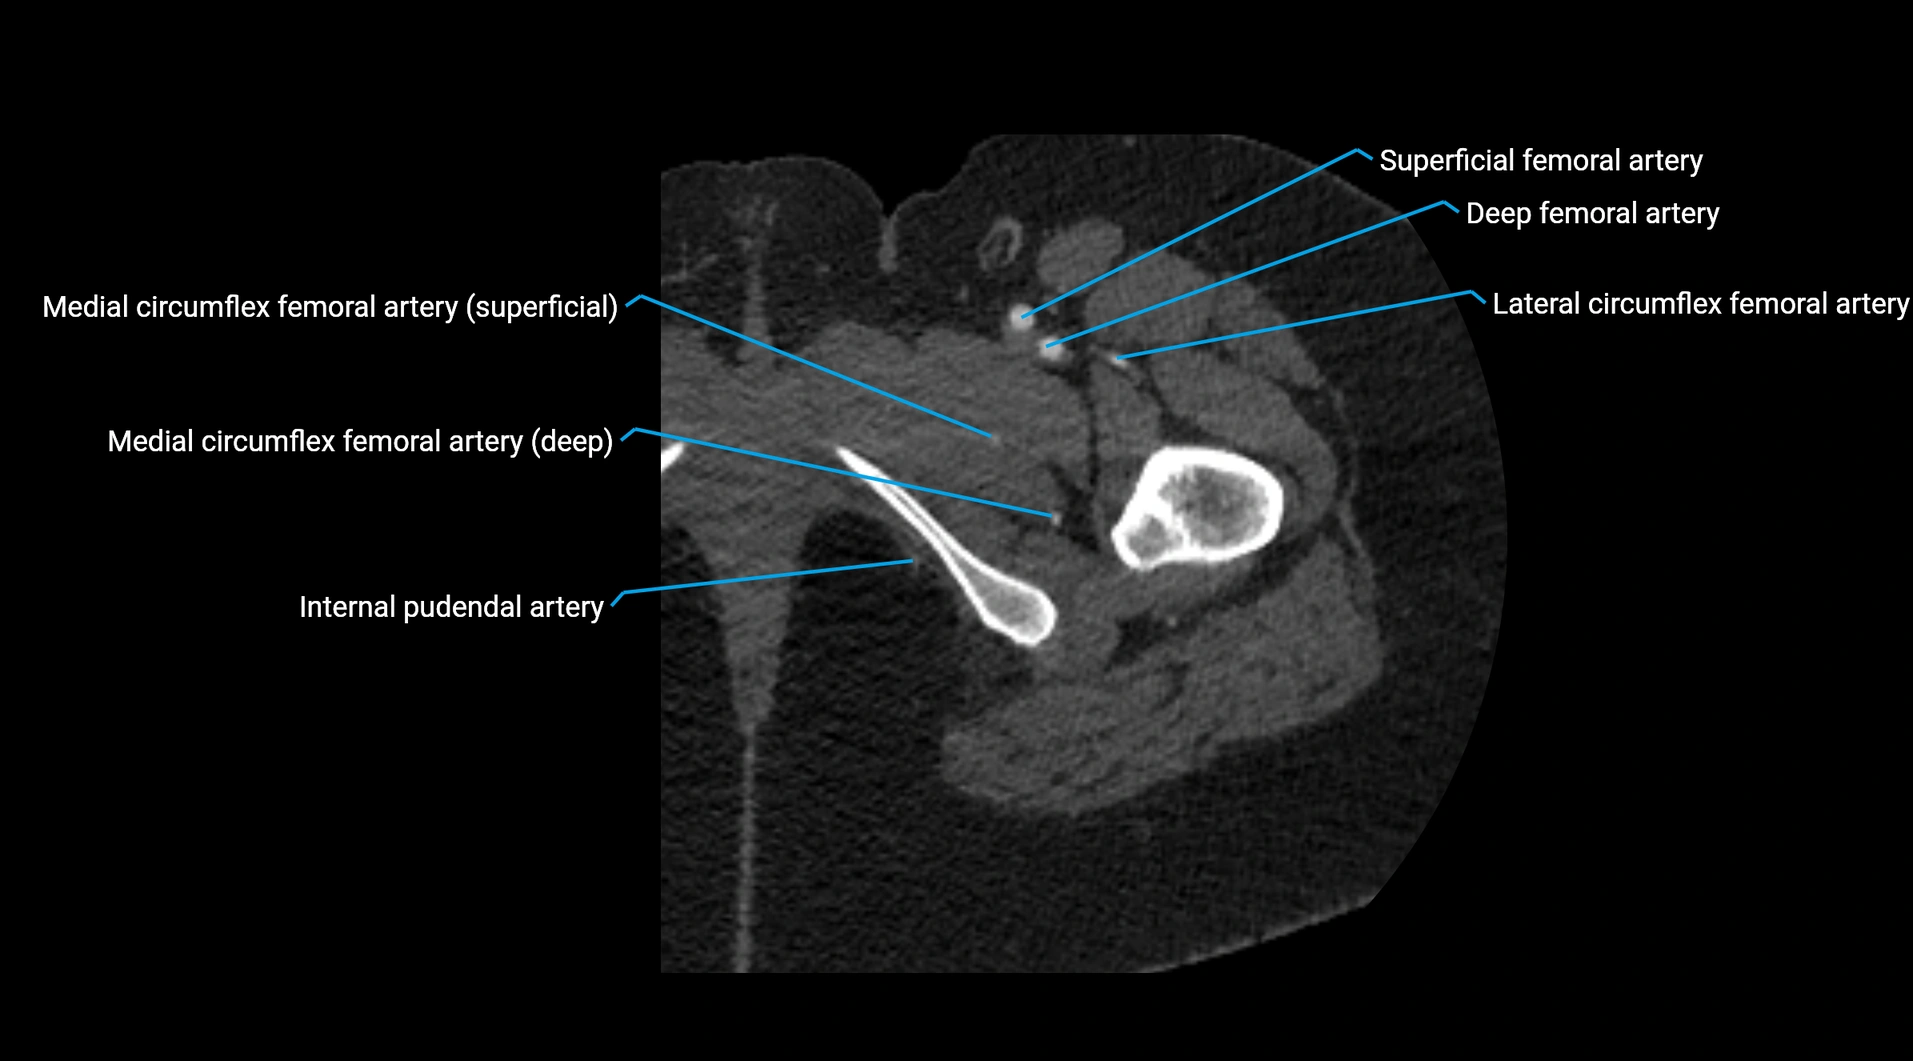

Contrast-enhanced CT (CTA):

• Gold standard for abdominal aortic imaging

• Provides excellent detail of lumen, wall, aneurysm, thrombus, and branch vessels

• Multiplanar and 3D reconstructions help in aneurysm measurement, stent graft planning, and dissection evaluation